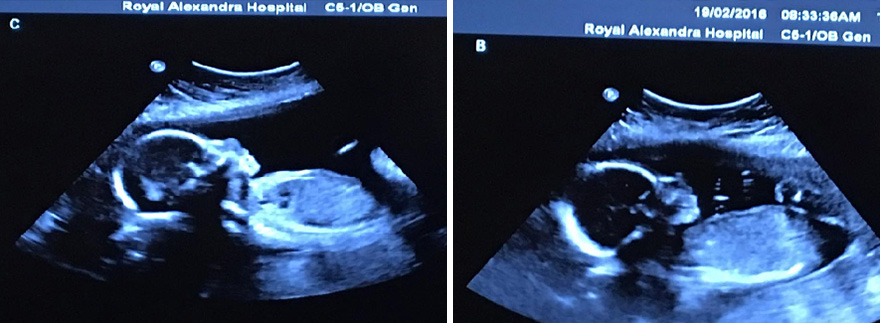

The chances of having spontaneous quadruplets (non-assisted) are predicted to be one in 729,000. As you could imagine, having identical siblings is even rarer. One lucky Canadian couple, Bethani and Tim Webb, beat the odds of one in 15 million and, on May 6th, 2016, gave birth to 4 identical baby girls – Abigail, Mckayla, Grace, and Emily. Now, two months later, the sisters have starred in an adorable nature-themed photo shoot and it’s making our hearts melt.